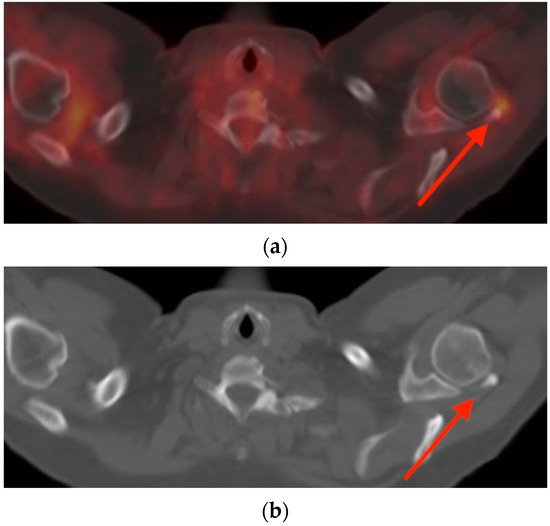

5.3. Hibernoma

6. Conclusions